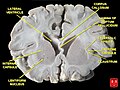

- Basal ganglia

- Includes: Nucleus caudatus, putamen, pallidum, subthalamus, substantia nigra

- Part of the forebrain.

- Caudate nucleus + putamen = striatum.

- Pallidum + putamen = lenticular nucleus.

Schematic overview (WC/blausen staff)

Section with descriptions (WC/SMH)